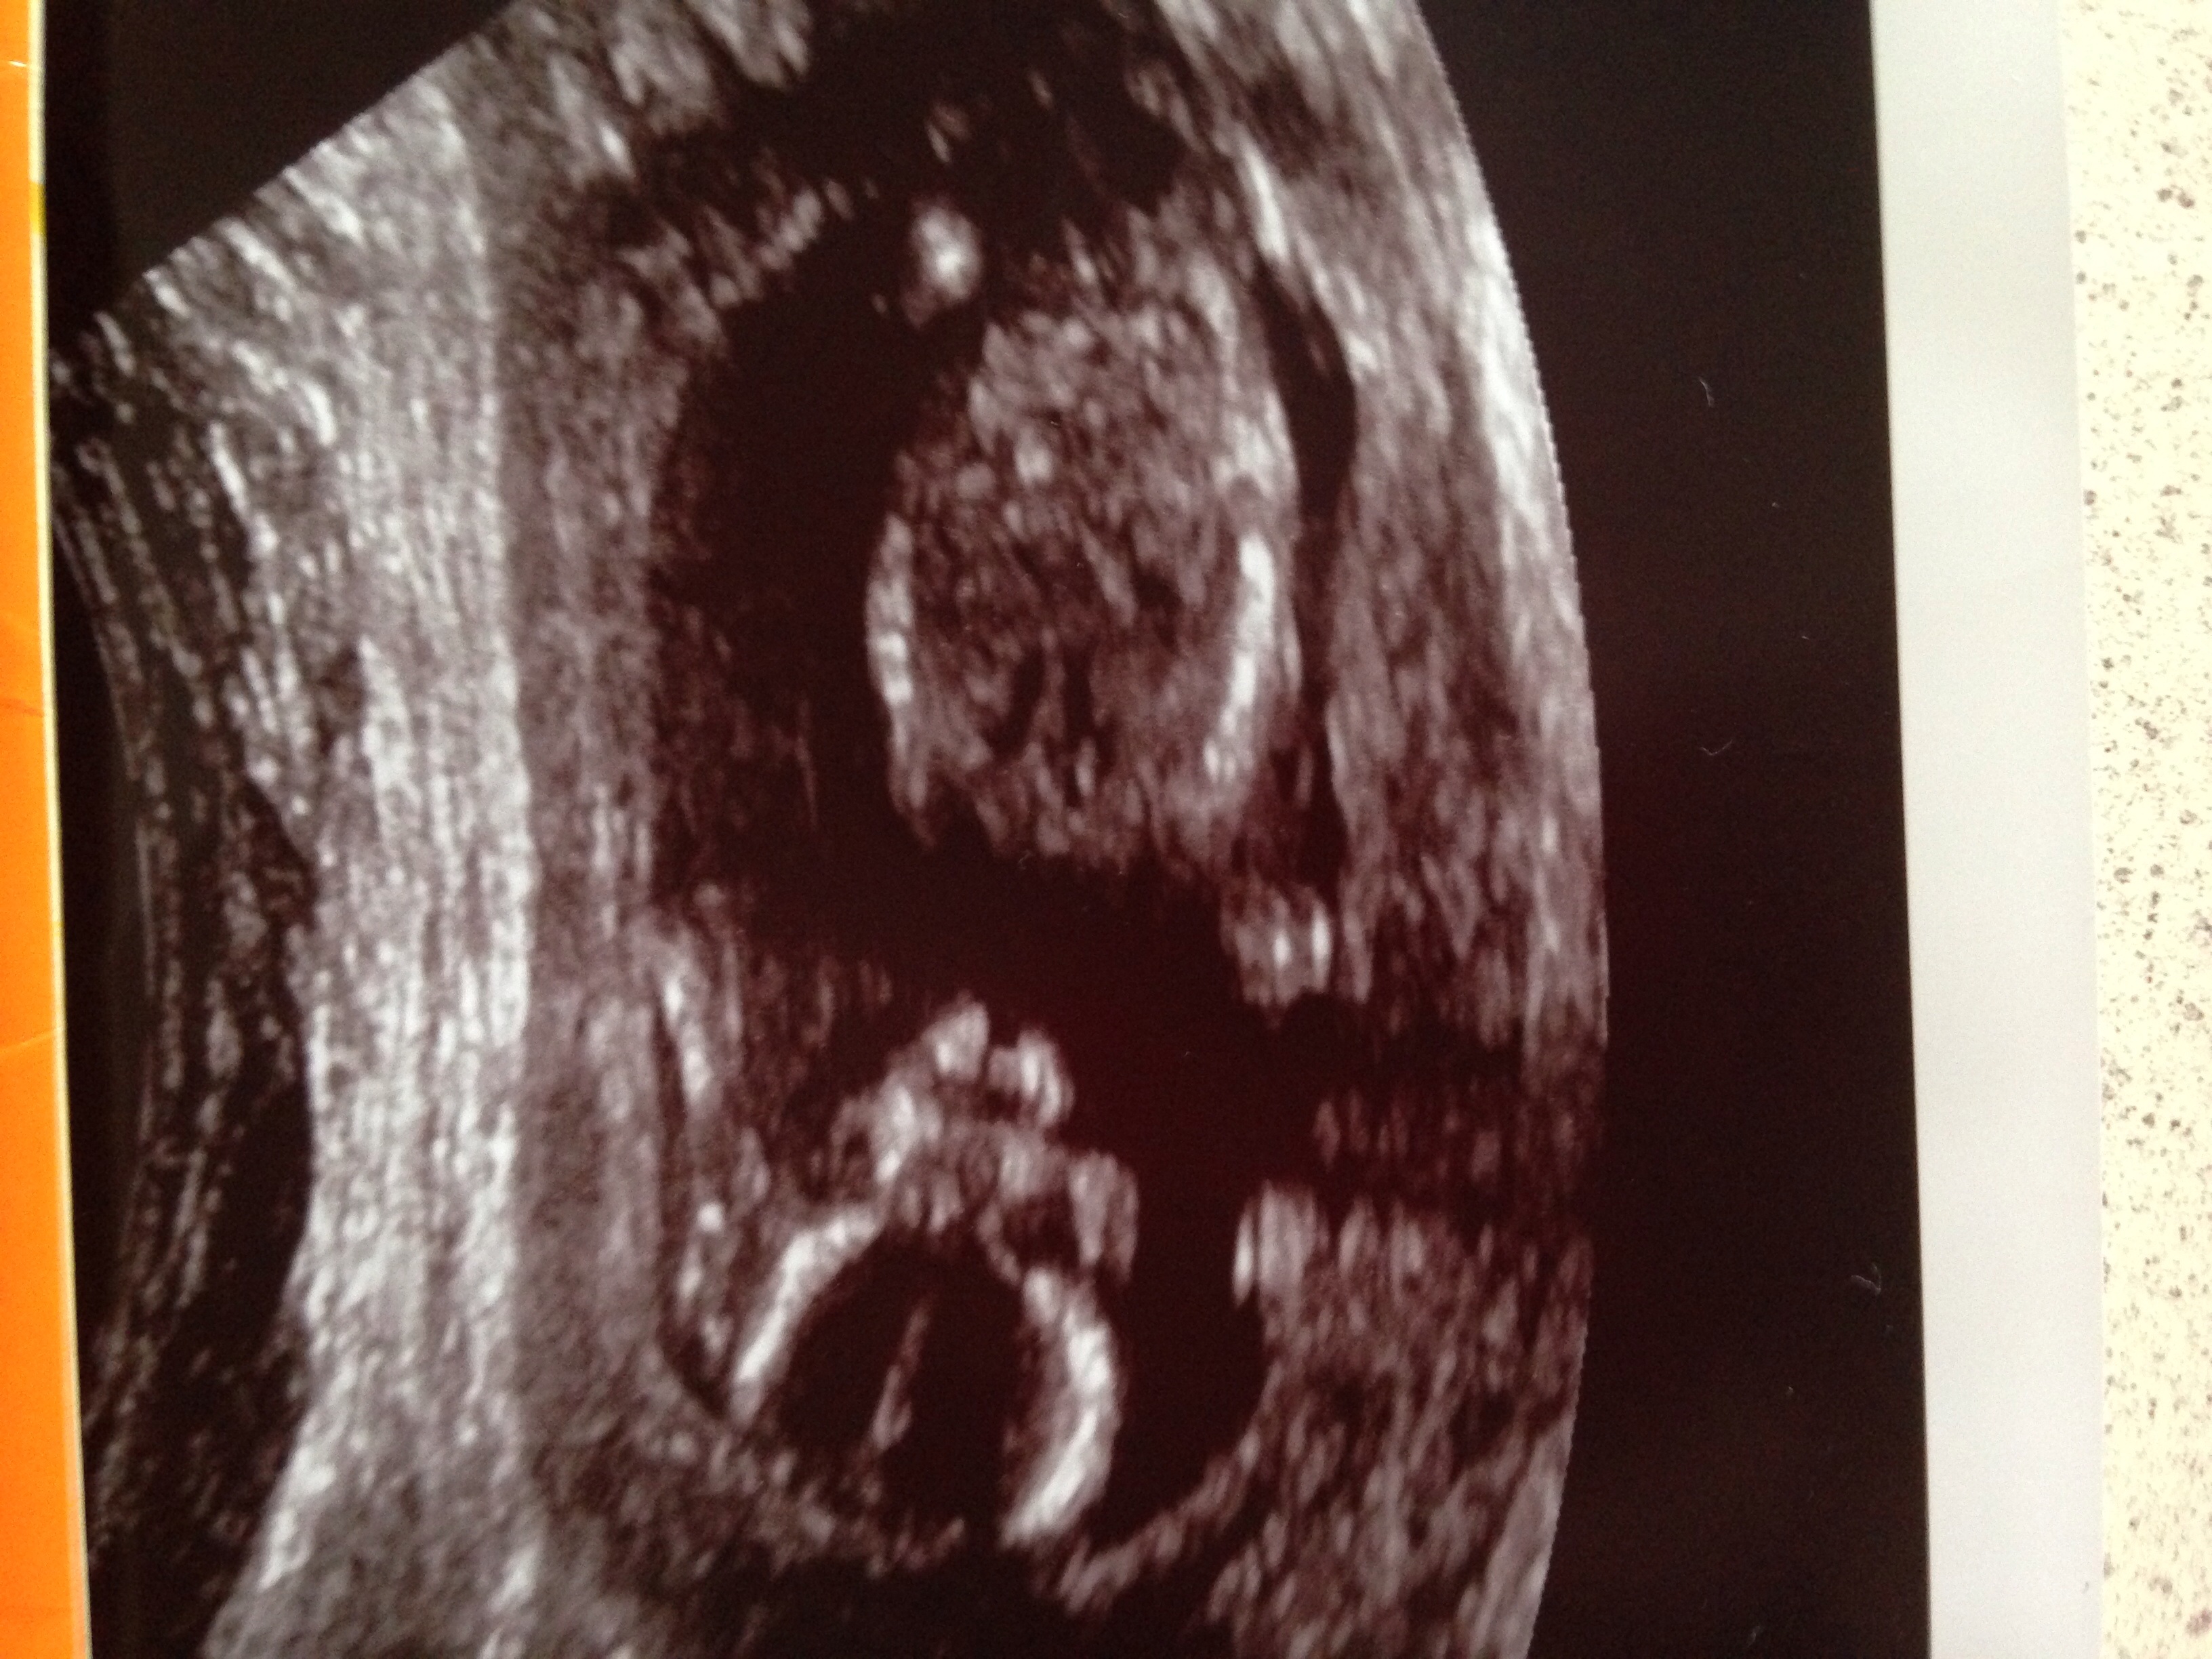

The first three are 12.1. The last two are 13.5.

Which line do you think is the nub? So busy!!!Attachment 21835